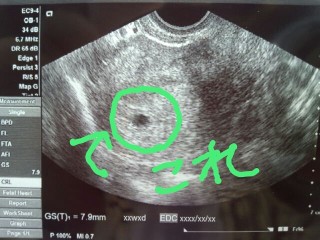

不妊治療(1年2ヵ月)を経ての妊娠です♪

本当は5w2dに検診予定だったのですが

4w6dに鼻・喉風邪をひいてしまい

心配になって受診♪

確認とれないかと思っていたら

胎嚢確認(7.9mm)出来ました

次は6w3dにクリニックです。

心拍確認とれますようにっ